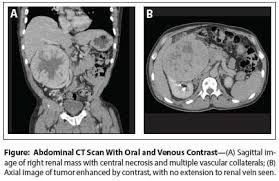

Kidney Renal Mass Surgery. Renal cell carcinoma or rcc is. Most of the masses found this way have no symptoms.

Patton mw et al. To treat or not to treat. Whenever possible surgery is the main treatment for kidney cancer that can be removed.

Whenever possible surgery is the main treatment for kidney cancer that can be removed. Treatment of kidney tumors depends on whether the tumor is large or a small renal mass see section on small renal mass. The smaller renal masses are often benign but larger ones are malignant. Whenever possible surgery is the main treatment for kidney cancer that can be removed.